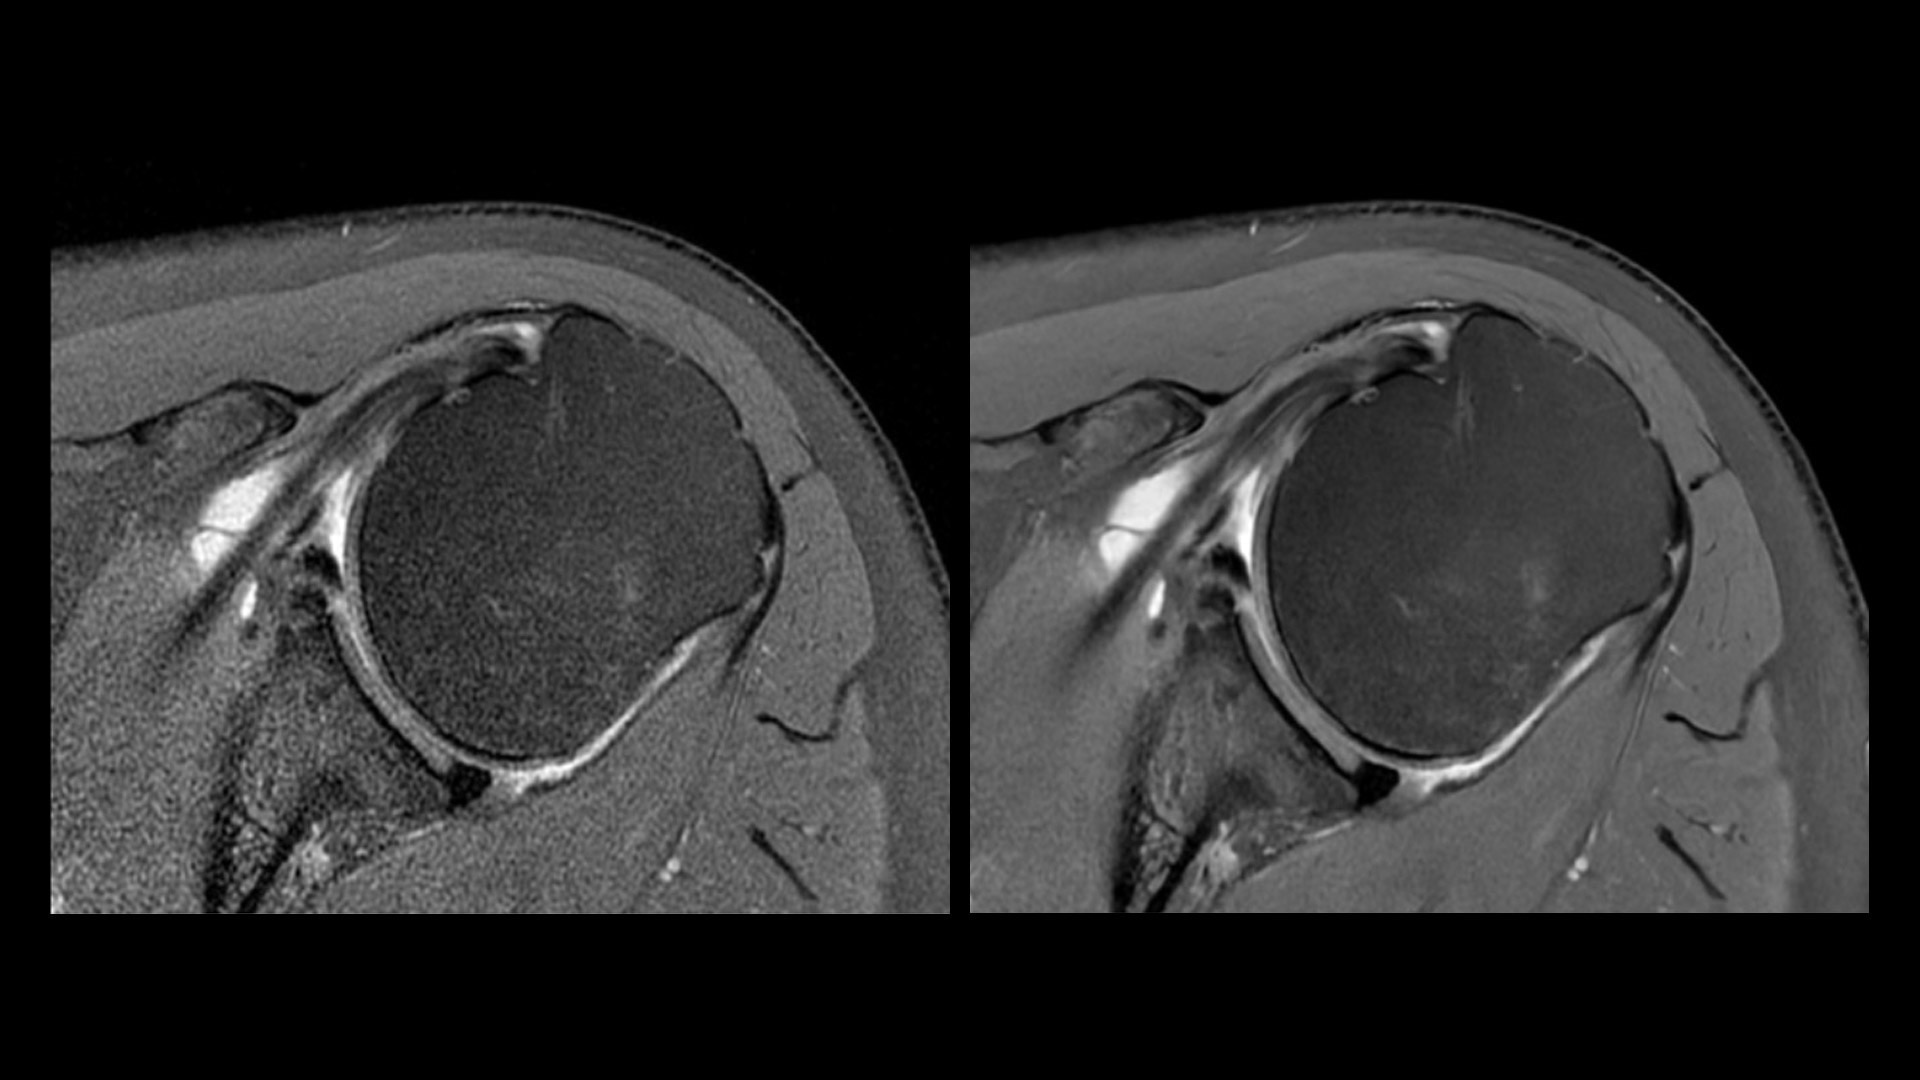

Effortless Recon DL

A portfolio of deep-learning applications designed to easily and quickly acquire and construct exceptionally clear images for confident decision making.

5. AIR Recon DL

AIR Recon DL leverages raw data and is integrated in the image reconstruction. This delivers improved SNR and sharper images by up to 60%.